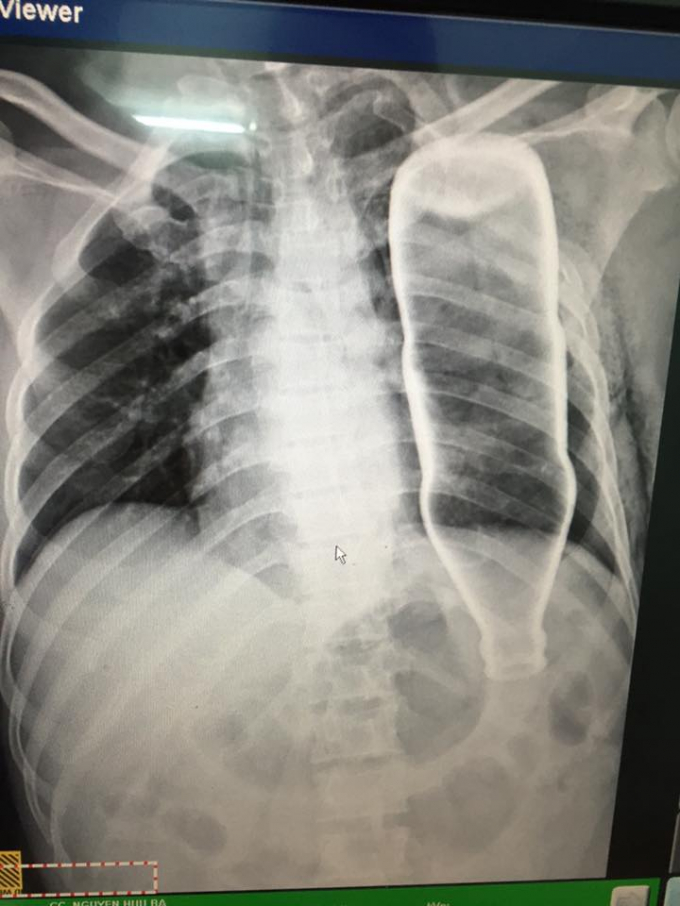

Sau khi các bác sĩ chỉ định chụp X-Quang cho bệnh nhân và hoảng hốt khi phát hiện trong vùng ngực có một vỏ chai thủy tinh, khiến ông B. bị gãy 2 xương sườn nhưng không có tổn thương nghiêm trọng khác.

Sau khi hội chẩn, các y bác sĩ đã lập tức thực hiện phẫu thuật để lấy vỏ chai ra khỏi lồng ngực bệnh nhân vào chiều cùng ngày.